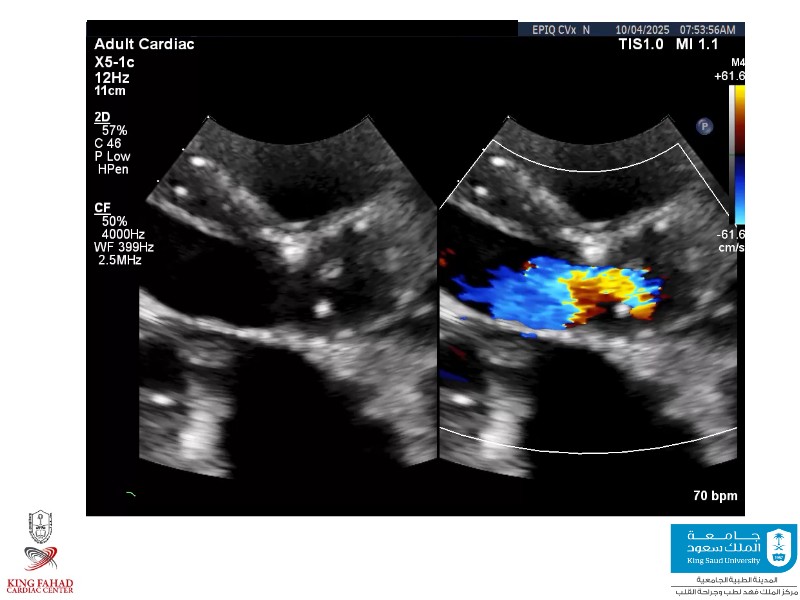

This session helps you anticipate and address complex scenarios such as mitral valve-in-valve, TAV-in-SAV, and valve-in-valve-in-valve procedures. Learn from expert case discussions that explore procedural strategies, technical challenges, and best practices to optimize outcomes in redo structural heart interventions.